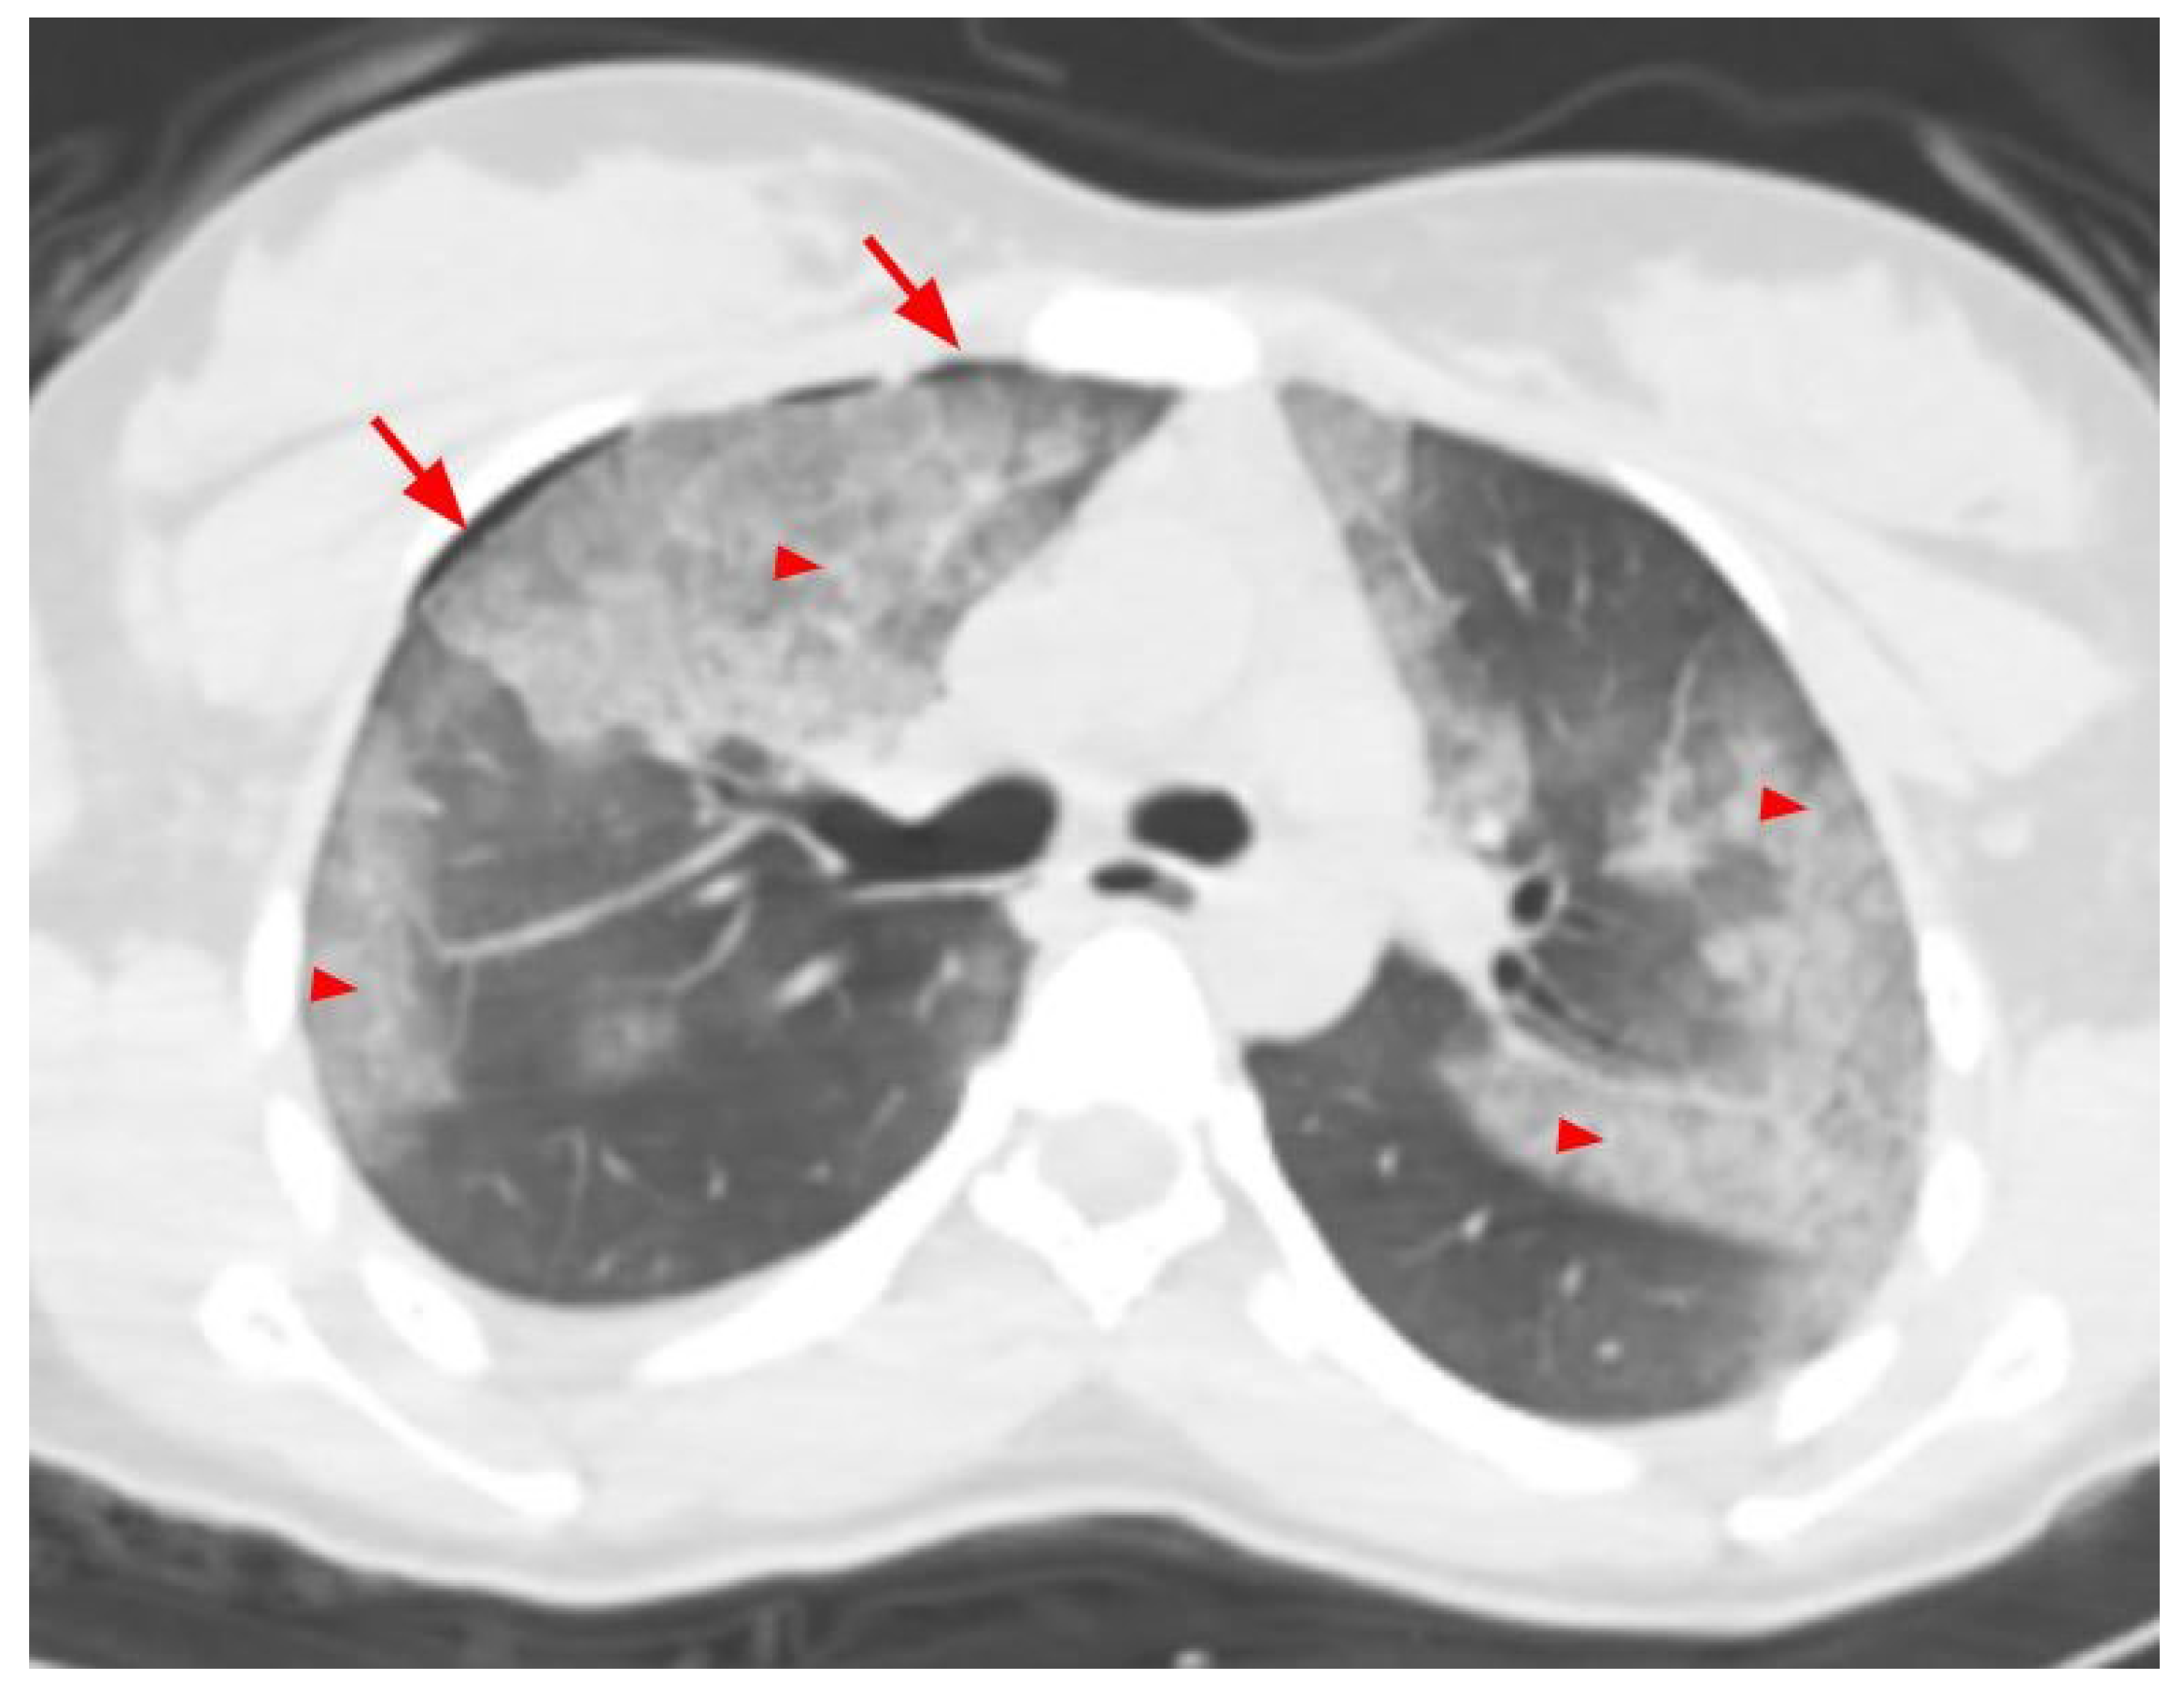

| Thorax | 7 (36.8) | 12 (63.2) | 45 (31.9) | 96 (68.1) | 52 (32.5) | 108 (67.5) | 0.667 |